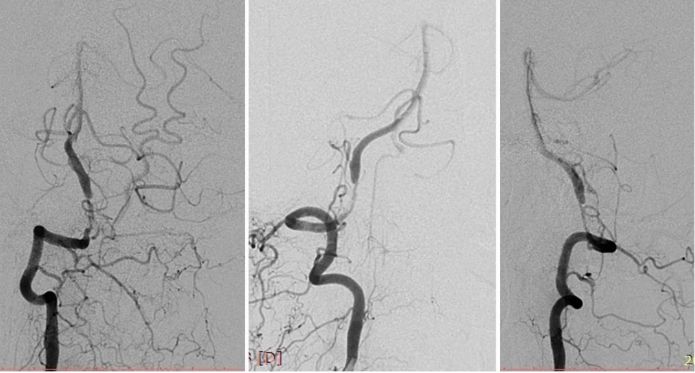

全麻下右股动脉入路, 将6F导引导管放至右椎动脉V2段远端,造影示右椎动脉V4段重度狭窄,狭窄率约为95%,狭窄长度13mm(图8)。

路径图下沿导引导管送入Transend微导丝(0.014″,300cm)越过病变至基底动脉中段,沿微导丝送入Gateway球囊(2.75mm×15mm)于狭窄处预扩张(图9)。

其后送入XT-27微导管,释放Neuroform EZ (4.0mm x 20mm )自膨式支架,造影提示支架释放后支架贴壁良好,前向血流TICI 3级(图10)。